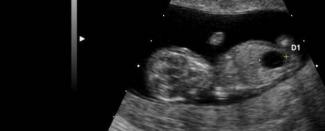

Nový PrenaTest je „zameraný výlučne na ženy od 12. týždňa tehotenstva so zvýšeným rizikom“, že budú mať dieťa s Downovým syndrómom. Zaujímavosťou je, že nenahrádza amniocentézu. LifeCodexx ho označuje ako „doplnok k ostatným prenatálnym diagnostickým analytickým metódam“. Avšak v skutočnosti tento test predstavuje pre dieťa s Downovým syndrómom zvýšené riziko potratu.